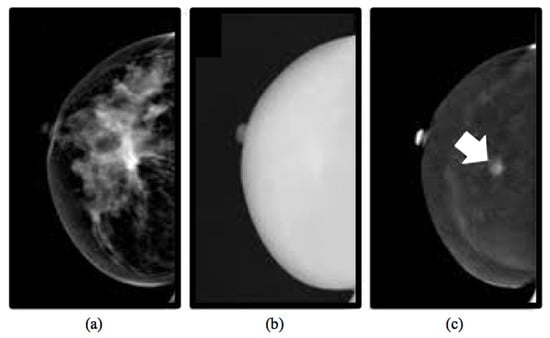

2.1.1. CESM Examination